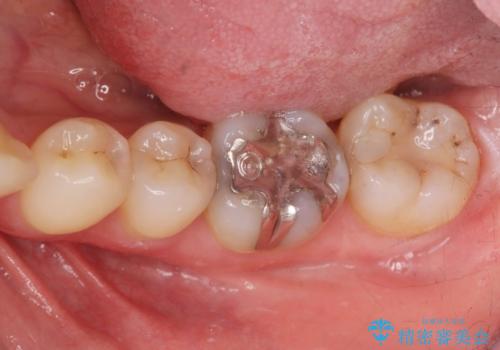

- 笑った時に見える銀歯を無くしたい、虫歯治療をしたい。とセラミック治療を希望され来院されました。

銀歯の除去・虫歯の除去を行ったのち、適合の良い精密なジルコニアセラミッククラウンを製作します。